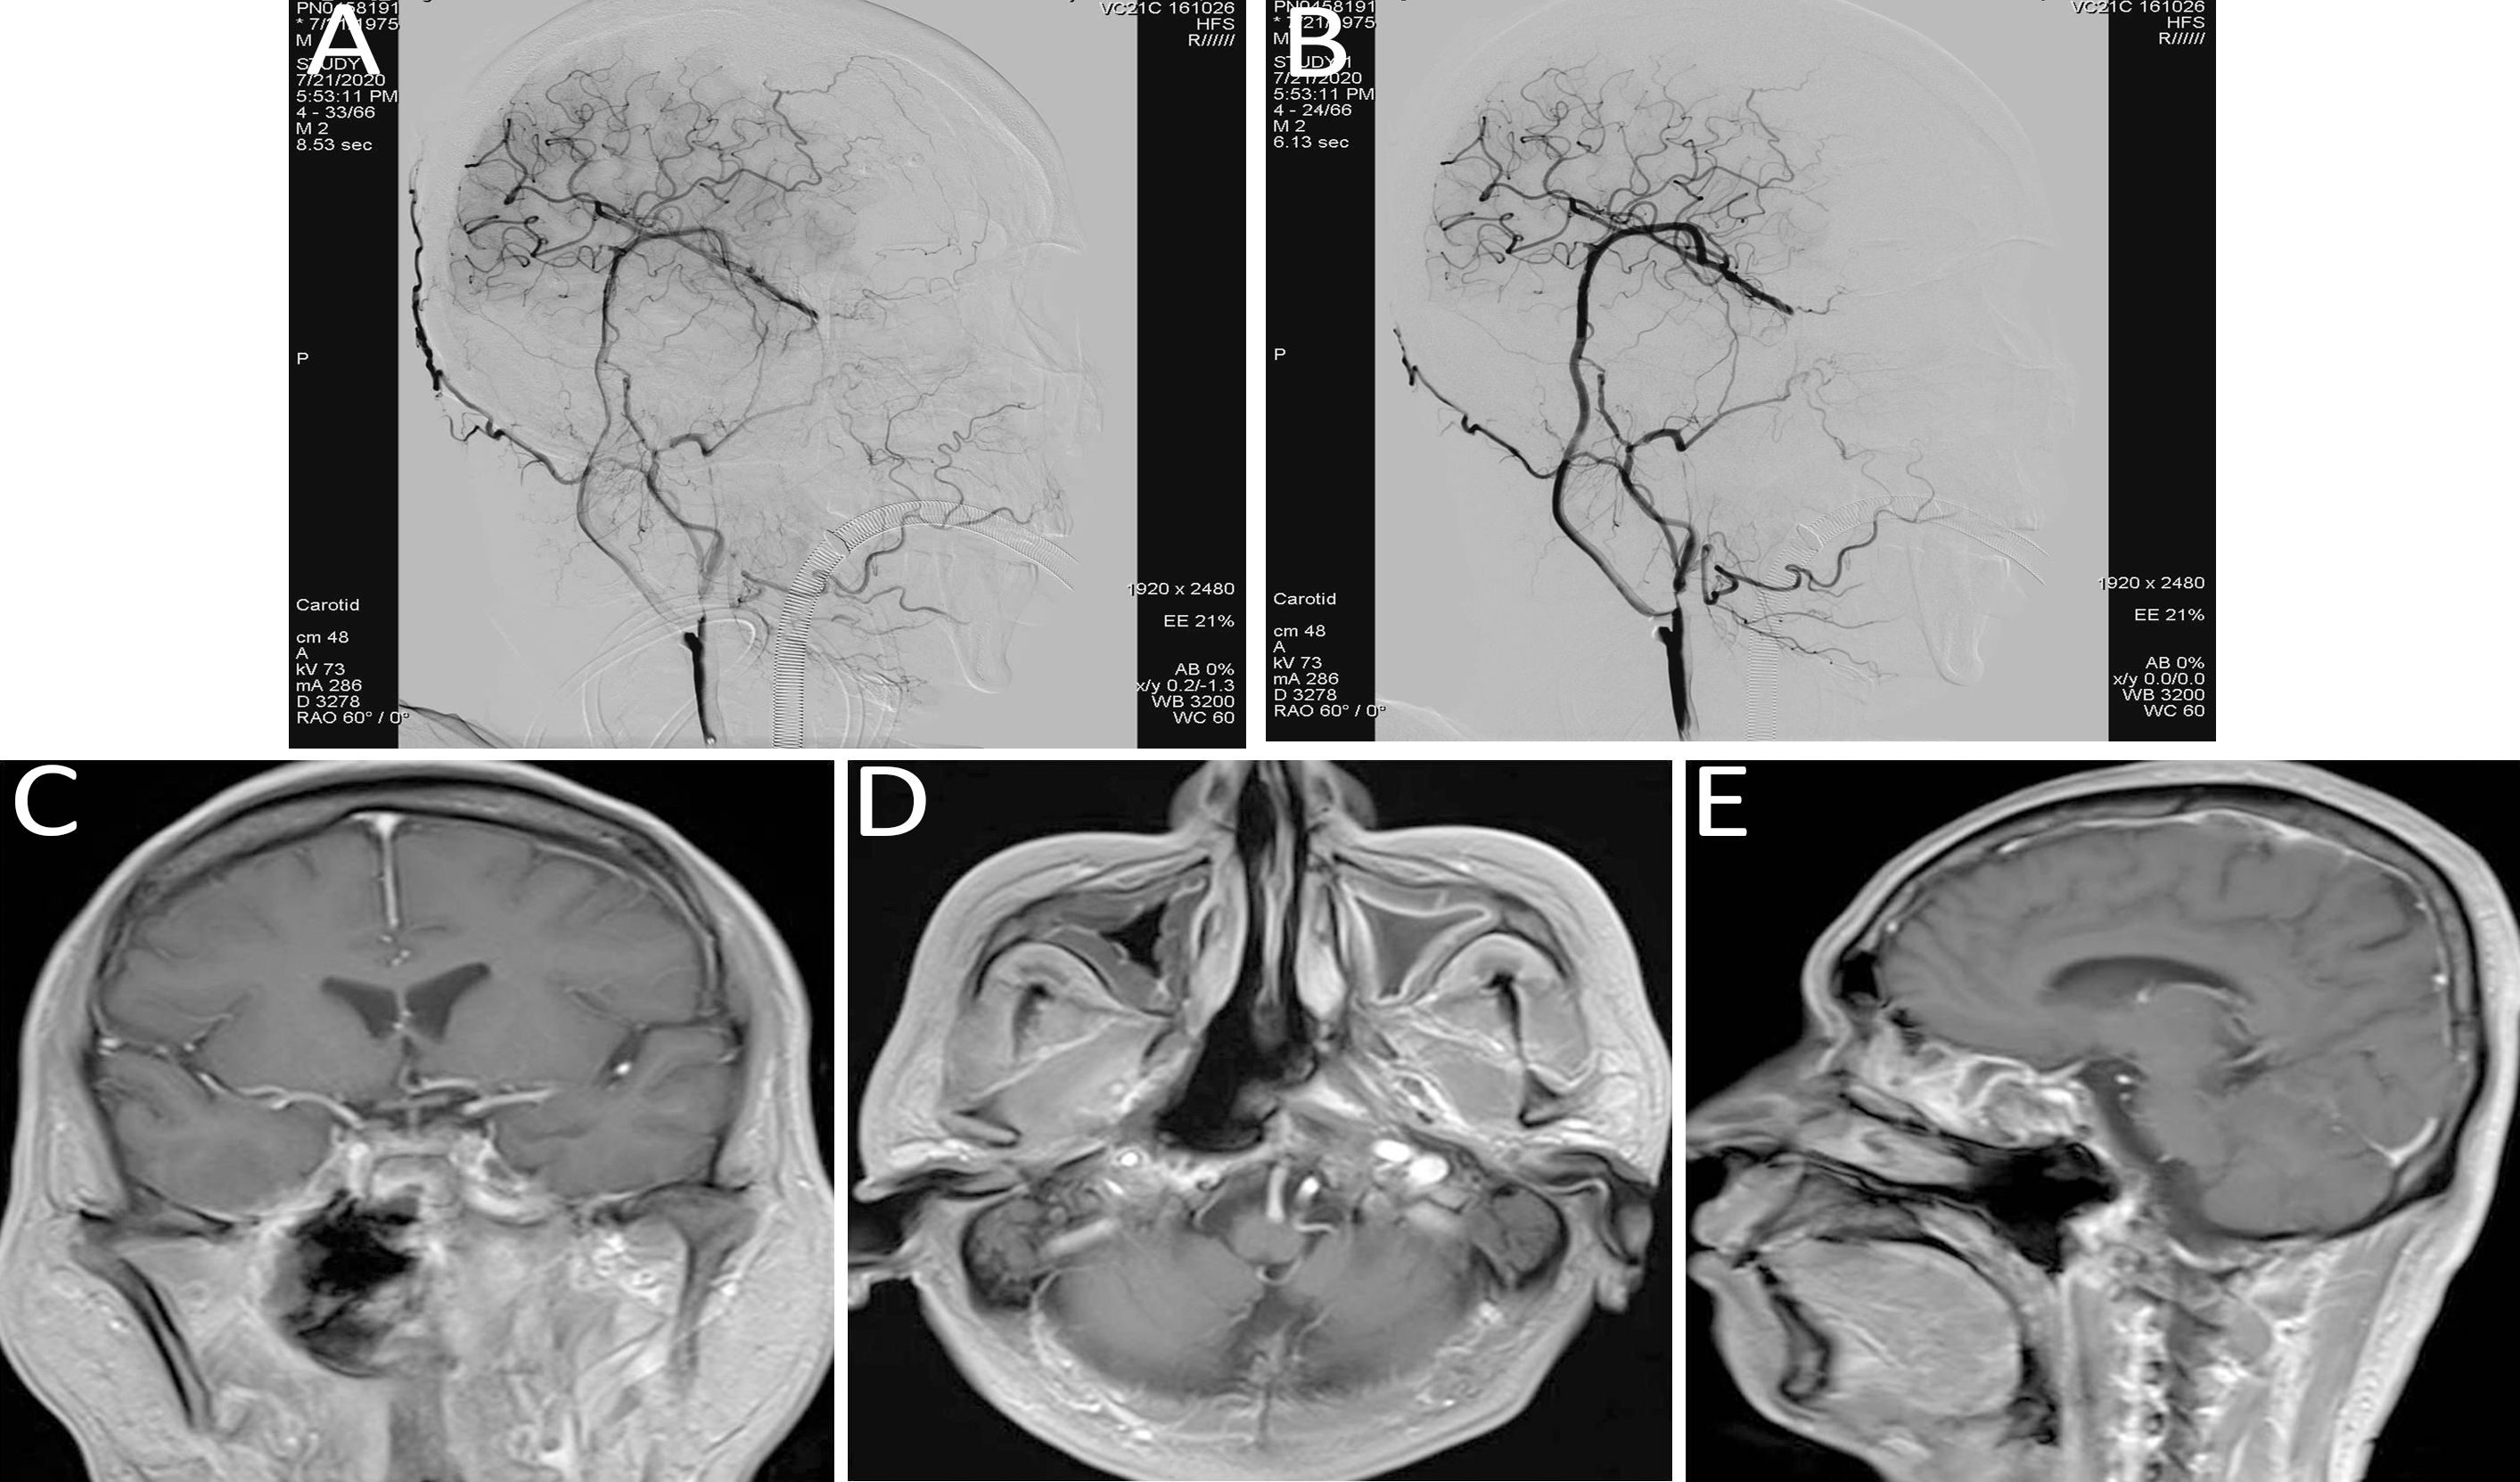

Figure 4

(A, B) Immediate post-bypass angiography confirmed patency of the bypass graft, with sufficient perfusion of the right middle cerebral artery and retrograde supply to the ophthalmic artery. No perfusion was observed in the right internal carotid artery at the cervical (C1), petrous (C2), and cavernous (C4) segments. (C–E) Follow-up head MRI demonstrated significant tumor shrinkage and satisfactory local disease control.

Immunotherapy and targeted treatment were continued. Follow-up MRI of the head demonstrated significant tumor shrinkage and favorable local disease control (refer to Figures 4C–E).

Case 2: A 49-year-old male with a history of right-sided hearing loss for one year and headaches for four months, following a five-year history of nasopharyngeal carcinoma underwent re-evaluation at this institution. Contrast-enhanced MRI indicated a space-occupying lesion in the right parapharyngeal space, consistent with recurrent nasopharyngeal carcinoma (refer to Figures 2D–F).

Considering the patient’s concurrent systemic conditions, arterial interventional infusion chemotherapy was selected. The chemotherapeutic agents, docetaxel and carboplatin, were diluted and administered via intra-arterial infusion (20 mL) through branches of the ascending pharyngeal artery or internal maxillary artery (refer to Figure 5).

Figure 5

Arterial interventional chemotherapy for nasopharyngeal carcinoma targeting the ascending pharyngeal artery or internal maxillary artery branches, with intra-arterial infusion of docetaxel and carboplatin (20 mL). (A) ascending pharyngeal artery; (B) internal maxillary artery branches.

Follow-up MRI demonstrated significant liquefaction and necrosis within the lesion cavity, along with a reduction in the size of the primary tumor, findings indicative of a PR (refer to Figures 2G–I).